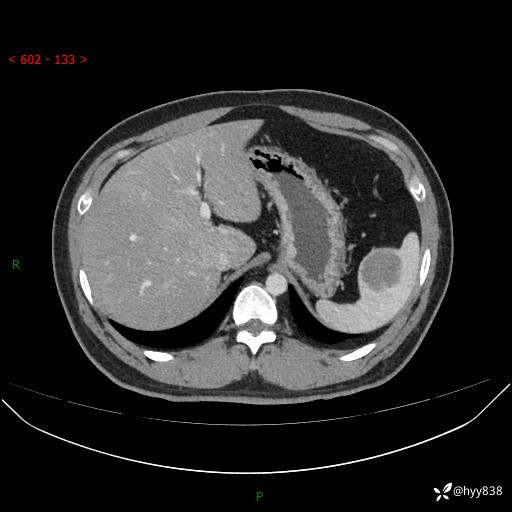

【患者信息】:31岁/男

【主诉】:超声发现脾脏肿物,为进一步诊治来我院,门诊以“脾脏占位”收入院

【检查】:上腹部CT平扫+增强